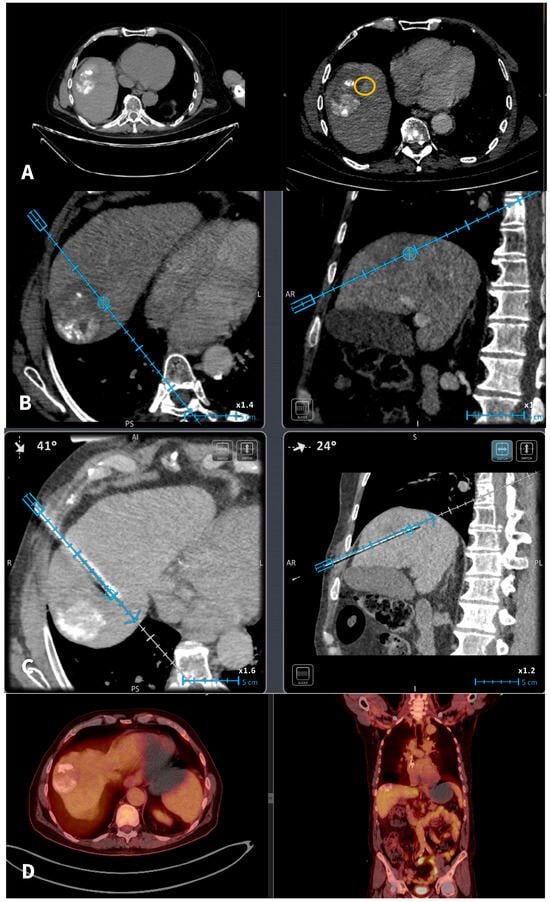

Figure 1. A 67-y-o male HCC patient who underwent in 2020 a combined therapy with MWA and transarterial chemoembolization. (A): In 2022 imaging follow-up depicts solitary hepatic lesion located in the hepatic segment VIII, 1 cm in diameter (recurrent HCC). The recurrent tumor was non-visible in the NCMCT scan. Axial CT scans pre and post-intravenous injection of Iodine contrast (portal venous phases) depicting the recurrent tumor (yellow circle) anteriorly and medially to the previously TACE + MWA zone of necrosis. (B): A commercially available electromagnetic navigation system with a marker software (blue circle) is used for tumor targeting and navigation of the microwave probe. (C): A commercially available electromagnetic navigation system with a marker software (blue circle) is used for navigation of the microwave probe. (D): Follow-Up PET-CT scan 6 months after treatment verifies total tumor necrosis.

The planning and placement of the microwave probe were carried out utilizing a commercially available electromagnetic navigation system designed for interventional radiology. As tumors were not visible in non-enhanced CT scans in all cases, iodinated nonionic contrast medium was intravenously injected; CT scans were obtained in arterial and portal venous phases in all patients. Subsequently, the series offering optimal tumor visualization on CT was transferred to the navigation system. Upon identification of the target lesion, a marker was placed on the screen of the navigation system of the exact size and at the exact location of the tumor target. The software provides the user with the option of moving the marker to the desired location and changing its size to meet the tumor characteristics. The additional value of marker option lies in the fact that, during the initial contrast-enhanced CT scan where the lesion is detectable, the marker can be used to delineate tumor’s location and size. In the subsequent scans where the tumor is not visible, the marker is there to delineate the target. Unfortunately, the marker is useful only for undetectable or inconspicuous hepatic tumors in non-enhanced CT scans, which are becoming visible in arterial or portal venous phase in CMCT. It was not able to be used until now in tumors that are not visible on CECT. In this study, all scans (both for setup and control) and needle movements were conducted during end-expiration apnea. A single microwave probe was used for ablating all tumors included in the current study. Once positioned accurately in the marker (i.e., tumor target), the ablation session was initiated and carried out based on coagulation charts provided by the manufacturer, considering factors such as tumor size, location, and the desired safety margin [Figure 1]. Goal of the ablation was a zone of necrosis including the tumor and minimum ablation margins of 5 mm for HCC and 10 mm for metastatic tumors. During probe removal from the liver in each session, track ablation was performed to minimize the risk of bleeding and tumor seeding. Post-ablation CT scans (pre and post-IV contrast medium injection in the arterial and portal venous phases) confirmed the ablation zone and assessed any immediate complications following the microwave ablation treatment. All patients were discharged from the hospital the following day.